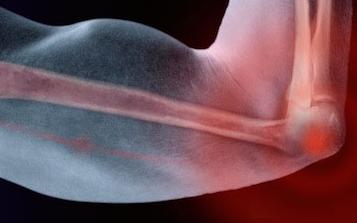

Одной из наиболее распространенных жалоб, с которой люди обращаются к врачу считается боль в локтевом суставе рук. В зависимости от характера и типа боли пациент может обратиться к травматологу, ревматологу или неврологу.

Боль может возникнуть при сгибании и разгибании руки, или не зависеть от движения. Болевые ощущения распространяются на сухожилия, мышцы, кости и суставы руки, выше места поражения.

Причины боли в локтевых суставах рук

Периодически возникающие дискомфортные ощущения в области локтя могут свидетельствовать о наличии множества различных заболеваний. Итак, рассмотрим основные причины, вызывающие боль в локтевом суставе: